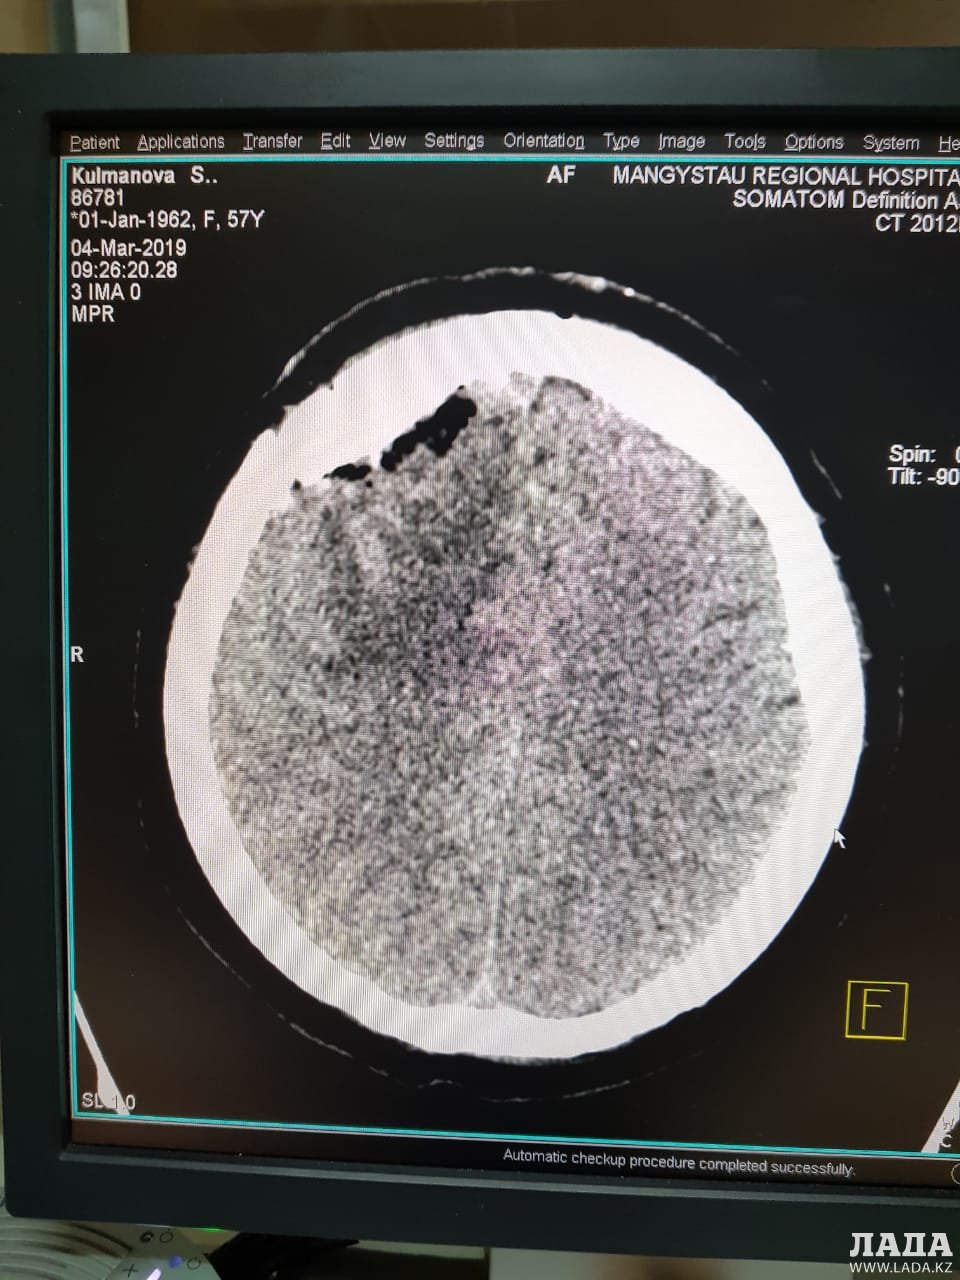

Опухоль мозга диаметром семь сантиметров удалили пенсионерке врачи Мангистау

Дополнительное обследование в аппарате компьютерной томографии (КТ) и магнитно-резонансной томографии (МРТ) показали у пенсионерки наличие отека правого полушария головного мозга.

- Врачи 28 февраля провели операцию по удалению опухоли в правой лобно-теменной области путем костно-пластической трепанации черепа пациентки. Операция прошла успешно, без осложнений, опухоль удалена полностью, - отметили в пресс-службе управления здравоохранения.